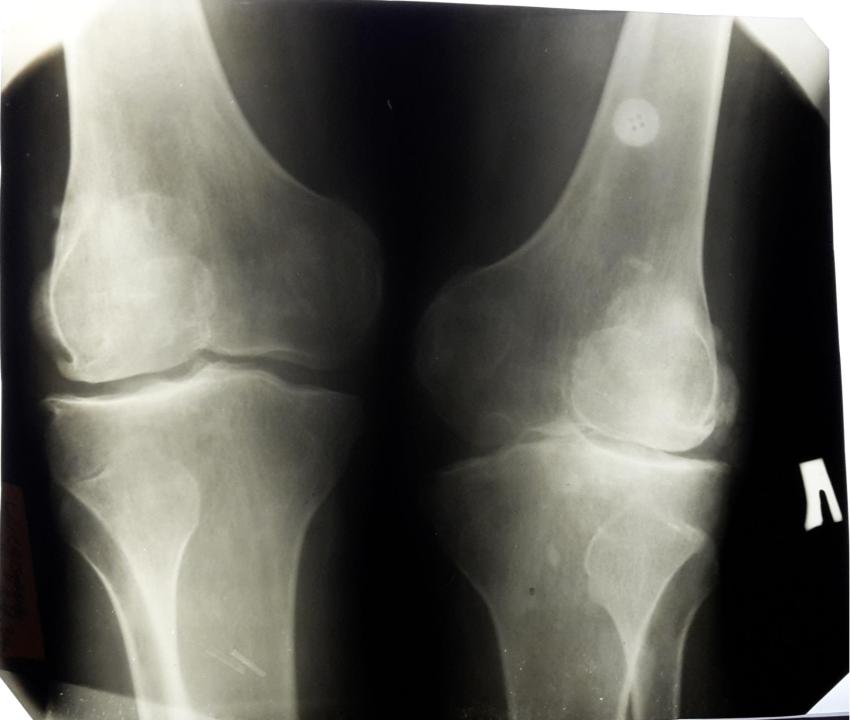

Пример деформирующего артроза коленного сустава.

Резкое сужение внутренней части суставной щели свидетельствует о полном разрушении там суставного хряща. Видны субхондральный склероз и кистозная дегенерация под суставными поверхностями.